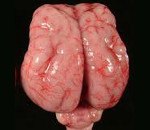

Лиссэнцефалия. Группа генетически обусловленных аномалий развития головного мозга, характеризующихся частичным или полным недоразвитием извилин и борозд коры больших полушарий, а также нарушением ее ультраструктуры. Выраженность и сочетания симптомов этого состояния различаются при разных формах заболевания, наиболее распространены судороги, глубокая умственная отсталость, нарушения глотания и гипотония мышц. Диагностика лиссэнцефалии может производиться ультразвуковыми методиками (в том числе и пренатально), компьютерной и магнитно-резонансной томографией, для наиболее распространенных форм возможно определение посредством молекулярно-генетического анализа. Специфического лечения не существует, используют симптоматическую и поддерживающую терапию.

Лиссэнцефалия - группа тяжелых аномалий развития головного мозга, которые сопровождаются недоразвитием коры больших полушарий с формированием пахигирии (наличием всего нескольких извилин и борозд) или агирии (полным отсутствием складчатости коры). Данная патология может выступать в качестве самостоятельного генетического заболевания или входить в симптомокомплекс других синдромов - например, Миллера-Дикера, Фукуямы и Уокера-Варбурга. Механизм наследования различных типов лиссэнцефалии может быть аутосомно-рецессивным, аутосомно-доминантным (в данном случае чаще всего имеют место спонтанные или герминативные мутации) и сцепленным с Х-хромосомой. Из-за многообразия механизмов наследования половое распределение нарушения неодинаково при различных формах патологии. Лиссэнцефалия является достаточно редкой генетической аномалией развития мозга, поэтому встречаемость определена только для наиболее распространенной первой группы нарушений - она составляет 11,7 случаев на 1 000 000 новорожденных. Для остальных групп лиссэнцефалии встречаемость не установлена, в том числе и потому, что во многих случаях плод с подобной патологией не вынашивается, и беременность самопроизвольно прерывается в первом триместре еще до определения наличия порока.